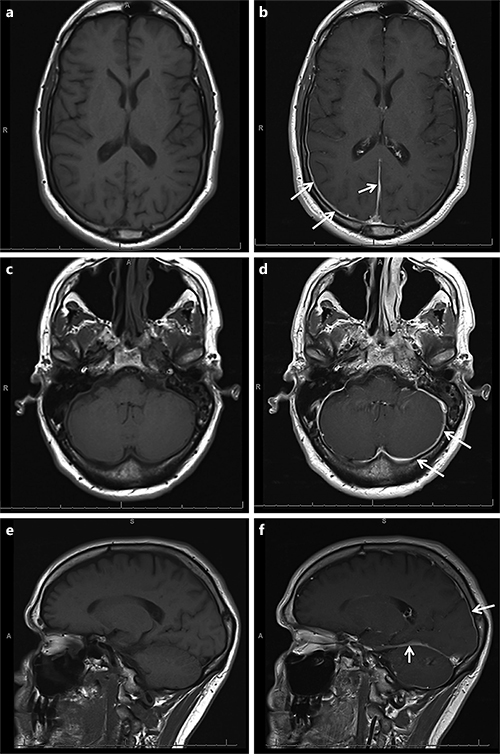

A Case of Hypertrophic Pachymeningitis Associated with Immunoglobulin Case Reports In Neurology Karger Articles from case reports in neurology are provided here courtesy of karger publishers. We report a very rare case of isolated accessory nerve palsy due to a large thrombosed aneurysm of the intracranial vertebral artery. Scilit source title profile of case reports in neurology scilit is a comprehensive content aggregator platform for scholarly publications. Published by karger online issn:. Case. Case Reports In Neurology Karger.

From karger.com